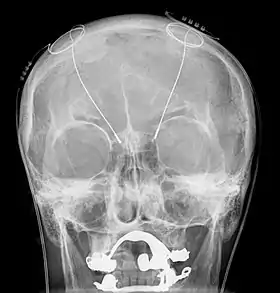

Wilder Penfield and Herbert Jasper used electrical stimulation of the human brain to find the places where their patients' seizures were coming from.[8] Dr. J. Lawrence Pool wrote "Effects of Electrical Stimulation of the Human Cerebellar Cortex" and described stimulation of a patient's brain.[9][10] In 1944, Reginald Bickford[11] is reported to have recorded the EEG of psychiatric patients who had had lobotomies.[12] After the 1949 Nobel Prize was awarded to António Egas Moniz for the procedure of lobotomy, a more precise method of destroying brain structures was pursued. In 1955, the placing of wires into a mentally ill patient was performed by Carl Wilhelm Sem-Jacobsen.[13] Stephen Sherwood also performed wire implantation.[14][15] In 1961, five patients had wires implanted to treat their mental illness and a precision leucotomy was performed for favorable results.[16][17]

Throughout the 1950s, many doctors continued to place wires or electrodes into the human brain.[18] They worked primarily on the brains of epileptic and psychiatric patients.[19][20][21][22] Robert Galbraith Heath placed electrodes in his subjects' brains in the 1950s to try to treat their mental illness and wrote several papers on his work of stimulating the various regions of the brain.[23] José Manuel Rodriguez Delgado also placed electrodes in his patients' brains. He called his inventions a "stimoceiver" and a "chemitrode".

- 2012: Cathy Hutchinson who is paralyzed had one hundred electrodes placed on the surface of her brain. With this brain–computer interface she is able to control a variety of devices.[32]